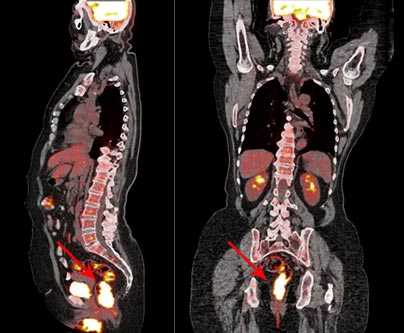

ПЭТ/КТ с 18F-фтордезоксиглюкозой: рак прямой кишки

ПЭТ/КТ всего тела с 18F-фтордезоксиглюкозой

проводят для:

На полученном при сканировании тела пациента изображении клетки опухоли видны как яркие пятна, так как они поглощают больше 18F-ФДГ, чем здоровые ткани. Врач имеет возможность сделать выводы о злокачественности образования, размерах и стадии процесса по насыщенности цвета, размеру, локализации и количеству «горячих очагов».